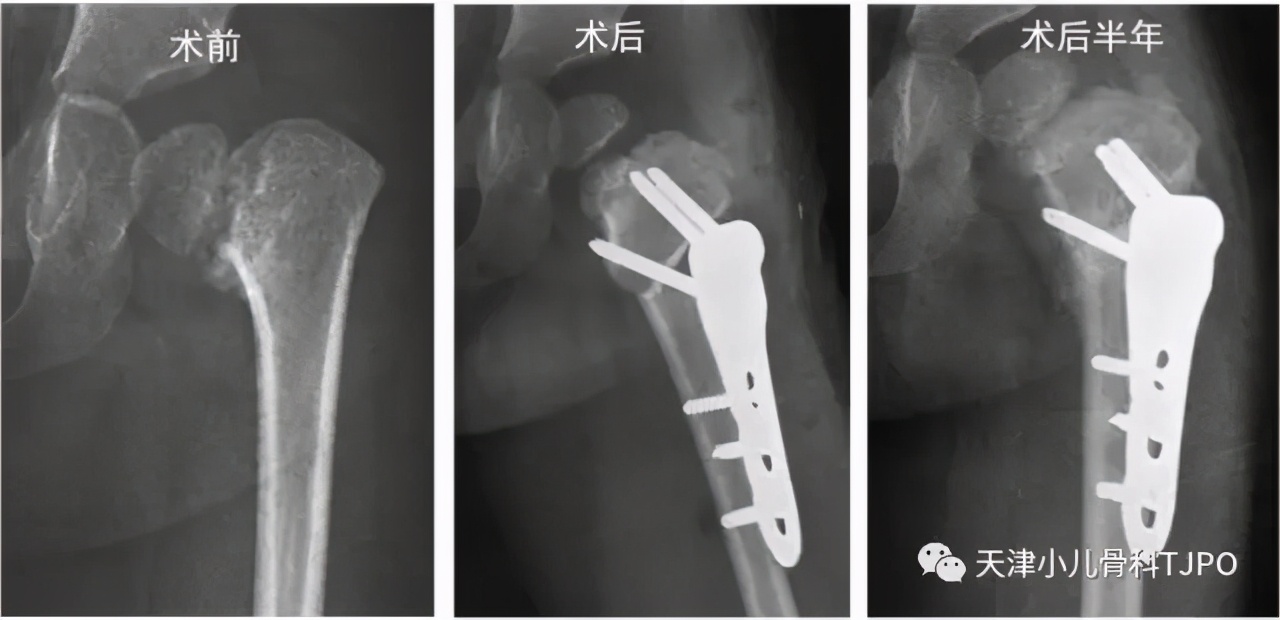

女孩,7岁时因步态异常就诊我院,拍片诊断为双侧发育性髋内翻,分期行双侧股骨近端外翻截骨术;术后2年,双侧截骨端愈合良好,股骨近端内侧骨质形态恢复正常,取出内固定。

通过外翻截骨术调整骺板方向,消除其受到的异常剪切力,避免了股骨头骺进一步滑脱。在颈干角获得矫正的同时,股骨近端内侧剪应力明显降低,再辅以内固定支持,能够获得薄弱区的愈合及硬化。我们取出内固定的指征是股骨近端内侧薄弱区完全愈合/融合,且呈现正常的骨质结构。